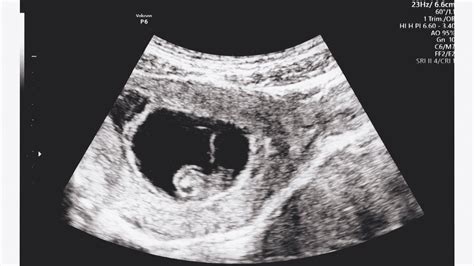

A magzatunk ultrahang vizsgálata kiemelkedően fontos kapcsolódási pont lehet leendő gyermekünkkel. Az ultrahang vizsgálathoz kapcsolódó áramlási vizsgálat során hallhatjuk meg először a szívhangját is. A szülészeti ultrahang vizsgálatok emellett fontos diagnosztikai felmérések, a hazai ellátási rendszerben 4 javasolt szűrő UH vizsgálat van.

A terhesség tényét az 5. héten is ki lehet mutatni, de az embrió szívműködése a 6. héttől észlelhető. Ezért bármennyire is izgatottak vagyunk, a 6. hét után érdemes először ultrahang vizsgálatra menni, ideálisan 7-9 hét között az utolsó menseshez képest.

Az első terhesgondozási alkalom során végezzük el az úgynevezett “nulladik” ultrahang vizsgálatot vagy másnéven koraterhességi ultrahangvizsgálatot (általában hüvelyi ultrahang vizsgálatra kell készülni). A vizsgálat legnagyobb jelentősége, hogy elkülöníthető, méhen belül vagy esetleg kívül látjuk-e a terhességre utaló petezsákot, ill. ennek során a petezsák, ill. az embrió méretéből kiindulva meghatározzuk a terhesség korát.

A koraterhességi ultrahangvizsgálat során megítélhetjük a petezsák elhelyezkedését, alakját, mérhetjük átmérőjét, a szikhólyag méretét és az embrió fejtető-farok távolságát (CRL), valamint áttekinthetjük a környező kismedencei területeket.

A vizsgálat célja a méhen belüli terhesség kimutatása. A terhességi kor függvényében a vizsgálat történhet hüvelyen vagy hason keresztül. Optimális ideje az utolsó menstruáció első napját követő 6-8. terhességi hét. Hüvelyi ultrahang vizsgálat esetén ajánlott a vizsgálat előtt a hólyag kiürítése, míg hasi ultrahang vizsgálatnál kedvezőbb a telt hólyag.

A 6. héten már jó eséllyel az embrió szívműködése is hallható lesz. Biztosabb képet mutat ilyenkor a hüvelyi ultrahang fejjel történő vizsgálat. Fontos tudni, hogy ilyenkor még hüvelyi ultrahanggal történik legtöbb esetben a vizsgálat.